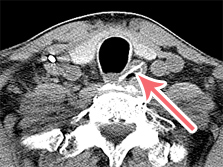

内視鏡で、胃粘膜に刺⼊しているアニサキス発⾒。

捕まえて引っ張っています。その後摘出されました。